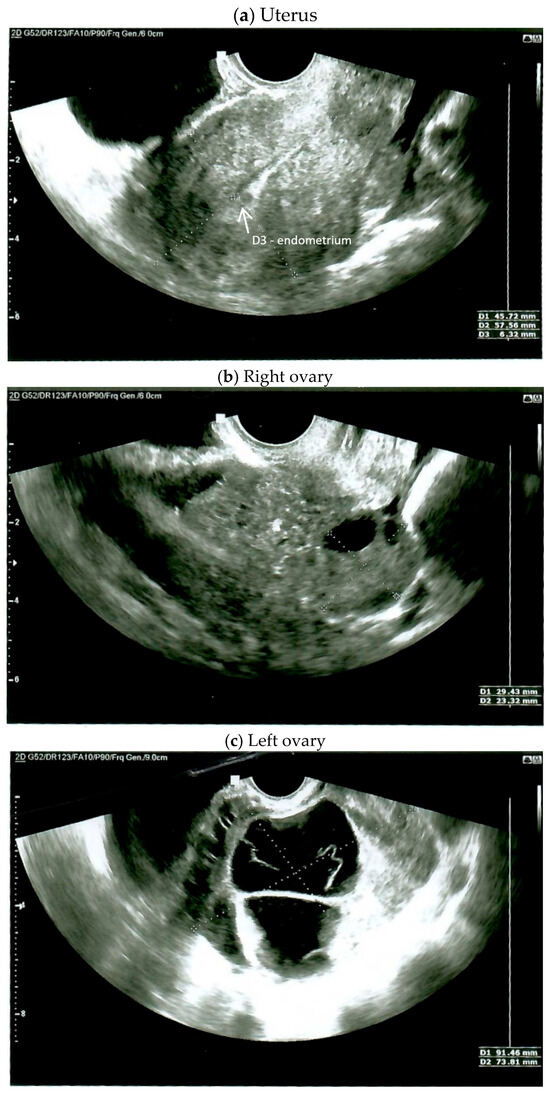

On the day of admission, the female was in good general condition. A gynecological examination demonstrated a normal-sized, retroverted body of the uterus, displaced to the right, with limited mobility. A tumor approximately 10 cm in diameter, with limited mobility, was detected behind the uterus on the left side. The ultrasound findings were as follows: the body of the uterus was homogeneous, measuring 45 × 57 mm; the endometrium was 6.3 mm thick and a small amount of free fluid behind the uterus was detected (Figure 1a); the right ovary measured 29 × 23 mm (Figure 1b); and the left ovary appeared as a solid-cystic tumor of 91 × 73 mm (Figure 1c). A multiple vascular pattern in the Doppler ultrasound was confirmed. The blood tests revealed a cancer antigen 125 (CA 125) level of 437 mIU/mL, a human epididymis protein 4 (HE-4) level of 481 pmol/L, and a Risk of Ovarian Malignancy Algorithm (ROMA) score of 95.6%. The patient qualified for surgical treatment.

Figure 1.

Ultrasound on the day of admission.